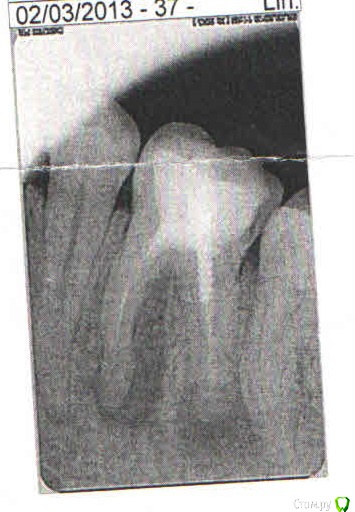

nashe72 Опубликовано 15 сентября, 2018 Поделиться Опубликовано 15 сентября, 2018 (изменено) Здравствуйте.Можно ли спасти этот зуб или только удаление? Боли нет, но постоянно чувствую дискомфорт в его области, пульсацию, "токанье". Также чувствую постоянный запах, думаю от него, так как другие зубы здоровы. Боюсь негативных последствий и очень жалко основной жевательный зуб. [ Изменено 15 сентября, 2018 пользователем nashe72 Ссылка на комментарий

St. Опубликовано 15 сентября, 2018 Поделиться Опубликовано 15 сентября, 2018 В этом зубе присутствует хроническое воспаление за пределами корня. Вероятность успеха лечения достаточно высока, но требует терпения (во-первых перелечивание каналов очень небыстрый и кропотливый процесс, во-вторых результат заживления будет видно не сразу потому что кость очень медленная ткань и чем дефект больше тем медленнее он соответственно заживает) и определенных финансовых вложений. Чтобы сохранить зуб нужно найти доктора который занимается лечением каналов, достать из зуба металлический штифт, старый материал из каналов, продезинфицировать это пространство и заново закрыть новым материалом. Потом этот зуб восстановить коронкой и через 6 и 12 мес делать контрольные снимки смотреть есть ли заживление и как быстро оно идет. 3 Ссылка на комментарий

DmitrySH Опубликовано 29 сентября, 2018 Поделиться Опубликовано 29 сентября, 2018 Сложное и кропотливое лечение. В умелых руках с большой вероятностью успеха. Желательно наличие оптики (микоскопа) у врача, т.к. есть подозрение на наличие фрагмента инструмента в переднем корне Ссылка на комментарий